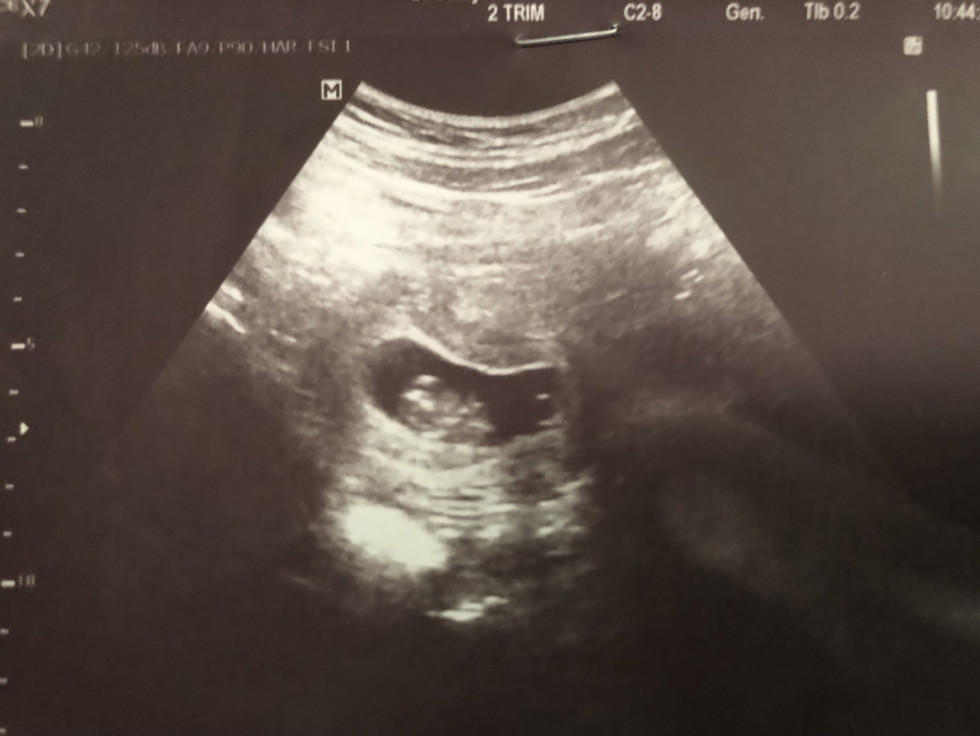

มีแม่คนไหนซาวเจอน้องตอน3-4เดือนนบ้างค่ะ

ของเราเจอตอน8สัปดาห์ แต่ตอนนั้นหมอนัดอีก4สัปดาห์เพื่อให้ชัดว่าเราไม่ได้ท้องลมค่ะ คุณแม่ใจเย็นๆนะ ตอนนี้บำรุเยอะๆ ห้ามออกแรงมากนะคะ

อุลตร้าซาวด์ครั้งแรก 9 week ค่ะคุณแม่ เจอตัวน้องแล้ว

ภาพซาวเราไม้เจอเด็กเลยตอน2เดือน

เราซาวครั้งแรกเจอค่ะ ตอน 13 w

เราซาวเจอตอนเกือบ11สัปดาห์

ขอดูภาพซาวหน่อยได้ไหมค่ะตอน8สัปดาร์เห็นแค่ถุงรกใช่ไหมค่ะ